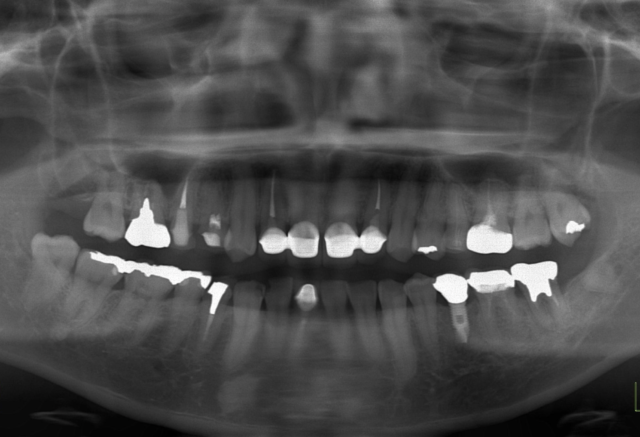

BEFORE

症例情報

通院時の年齢

40代

性別

女性

通院目的

前歯の見た目が気になる

矯正はしたくない

処置内容

上顎2~2と下顎右下1の補綴

右上2左上2の歯周外科処置

費用

約65万円

デメリット

右上2と左上2の歯肉の後戻りの可能性がある

備考

右上2と左上2の歯肉形態を修正し、上顎2~2を補綴することで、審美性を獲得した。

右下1は右下2と左下1の形態を少し修正して補綴している。

術前